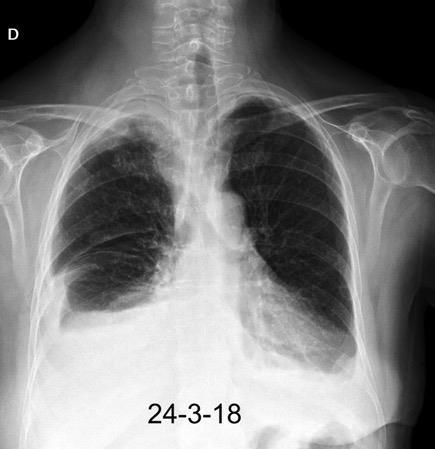

Radiografía AP en politraumatizado con enfisema subcutáneo severo.

Kumar H M,et al. Ginkgo leaf sign and subcutaneous emphysema.BMJCase Rep .2018